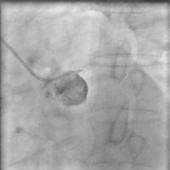

腎動(dòng)脈閉塞是指腎動(dòng)脈主干或較大分支由于血管壁或血液因素導(dǎo)致腎動(dòng)脈腔內(nèi)發(fā)生的完全閉塞,按起病緩急分為急性及慢性。急性腎動(dòng)脈閉塞經(jīng)常是因?yàn)榍槐谘ㄒ鸬乃ㄈ蚰I動(dòng)脈急性血栓形成,慢性腎動(dòng)脈閉塞多在腎動(dòng)脈狹窄基礎(chǔ)上逐漸出現(xiàn)完全堵塞。